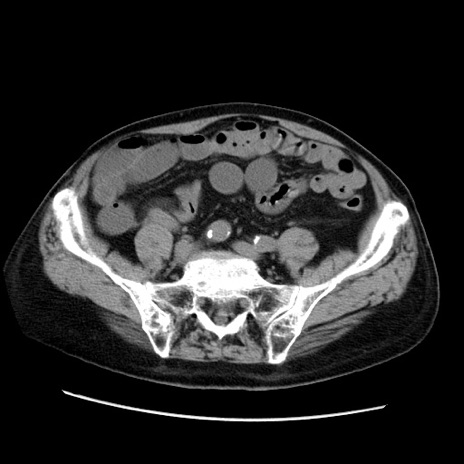

症例21(横断像)

【症例】70歳代男性

【主訴】腹痛

【現病歴】肝硬変・肝細胞癌にてかかりつけの方。約9時間前に食後より腹痛出現。症状が徐々に増悪し、嘔吐出現したため来院。

【既往歴】肝硬変、肝細胞癌(RFA、TACE後)

【身体所見】意識清明、表情苦悶様、BT 36℃、BP 129/78mmHg、P 88bpm、SpO2 97%(RA)、右上腹部から心窩部にかけて圧痛あり、反跳痛なし、筋性防御あり。

【データ】WBC 5800、CRP 0.16